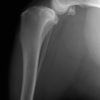

雑種 5歳

左後肢の挙上を主訴に来院されました。触診にて両関節の前方引き出し兆候、両膝蓋骨の内方脱臼を認めました。関節液検査より免疫介在性多発性関節炎は否定的でした。レントゲン検査にてfat pad signを伴う関節炎が認められたことから、前十字靭帯断裂と膝蓋骨内方脱臼(左GradeⅢ 右GradeⅢ〜IV)併発と診断し、手術を行いました。

手術は片足ずつ行い、両膝とも術中の関節鏡検査にて前十字靭帯の完全断裂と半月板損傷を確認しました。TPLO、半月板切除と滑車溝形成を始めとした膝蓋骨脱臼整復術を実施いたしました。膝蓋骨の安定化を測るために外側支帯を強固に縫合し、内側支帯は切除し縫合せずに開放状態にしています。

術後の歩行状態は良好です。

術前左後肢側面像

術前正面像

術後左後肢側面像

術後左後肢正面像

術前のTPAは左後肢33.1°右後肢26.8°でしたがTPLO実施により左後肢5.5°右後肢12°に矯正されました。